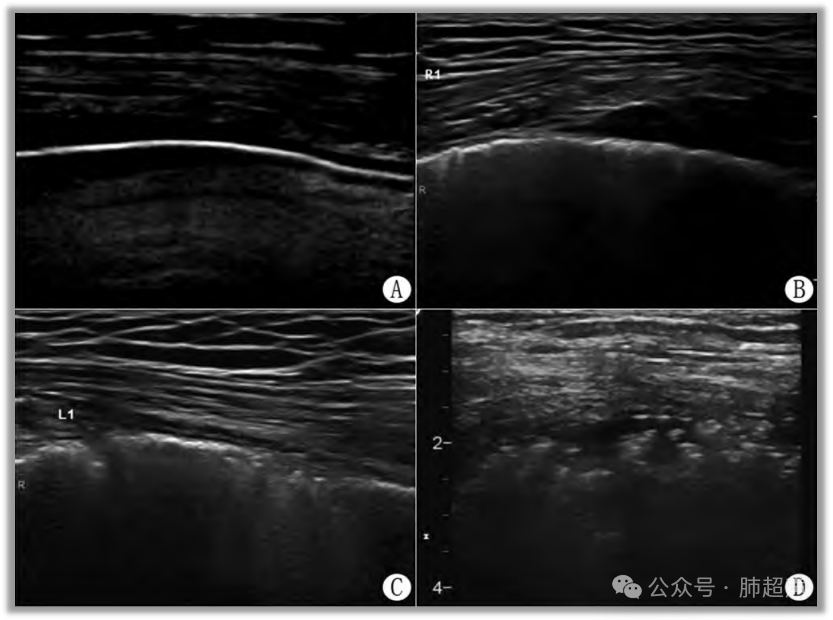

(3) 轻症ILD可表现为局部(早期以肺底常见)B线,胸膜线不均匀;典型弥漫性肺间质纤维化可表现为双肺弥漫性B线及胸膜下间质异常,B线数量和胸膜线特征与ILD严重程度相关(图4)

图4  间质性肺疾病及肺间质纤维化超声表现

注:A. 结缔组织病相关间质性肺疾病(ILD);B. 轻度ILD的胸膜线;C. 重度弥漫性肺间质纤维化的胸膜下间质呈典型颗粒状表现。